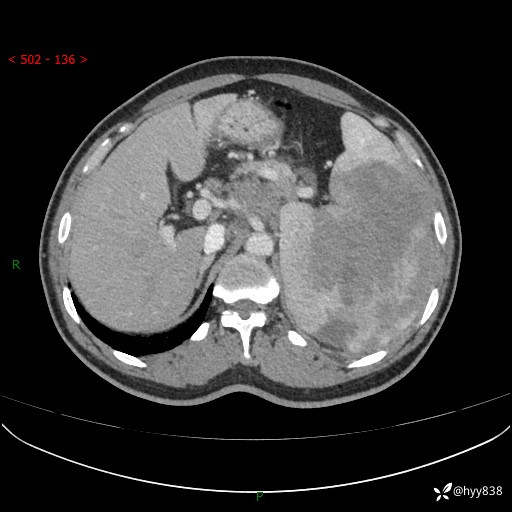

增强(动脉期+静脉期)